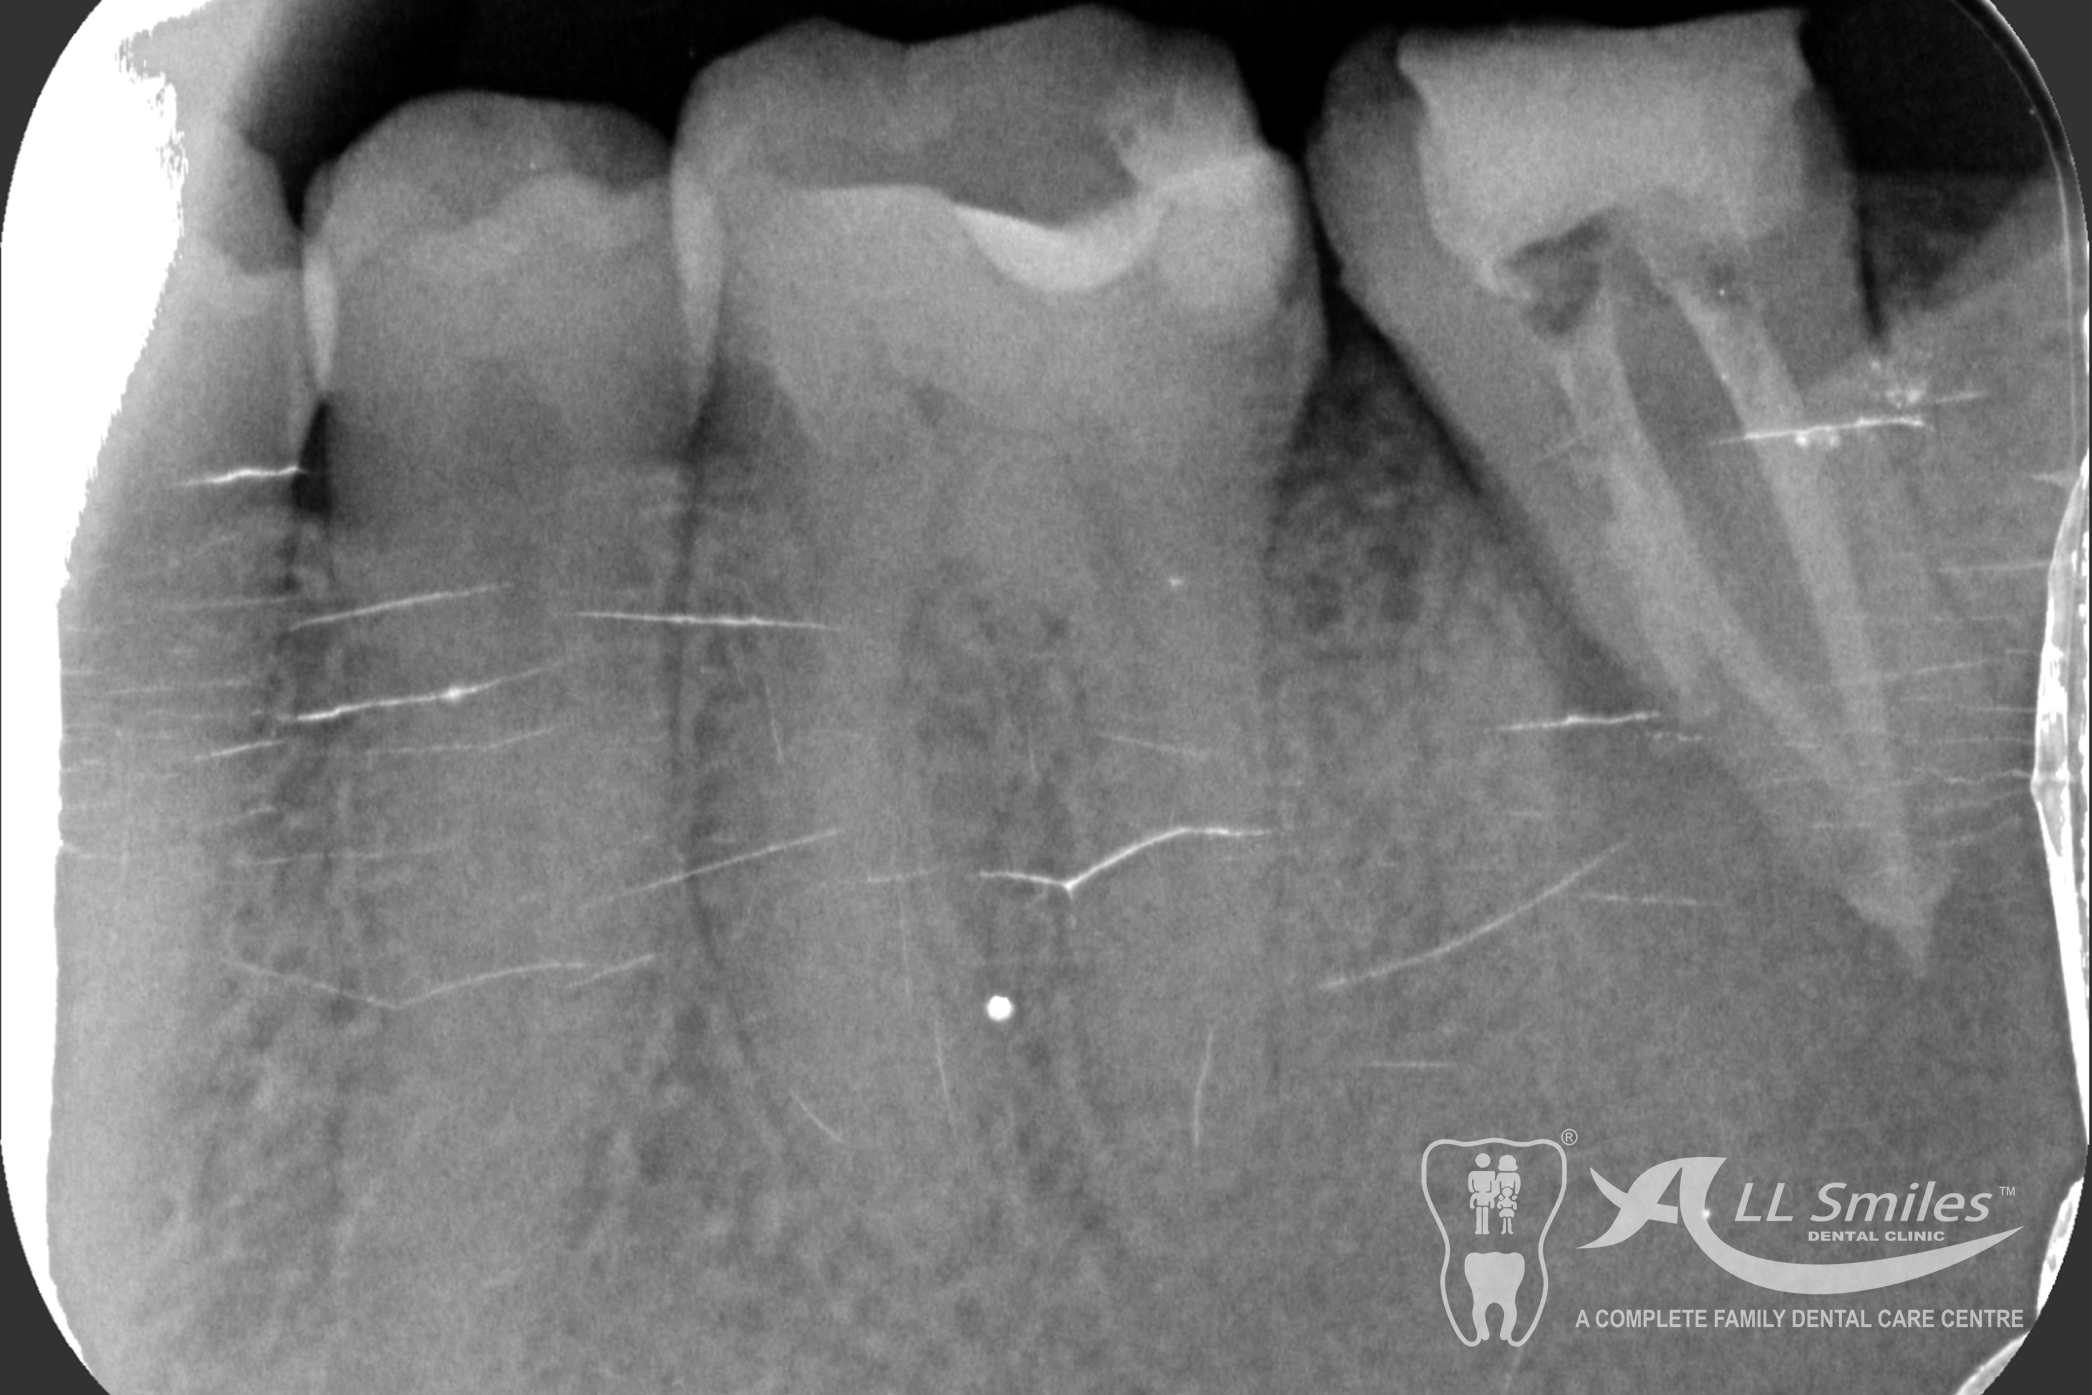

Root Canal Gallery